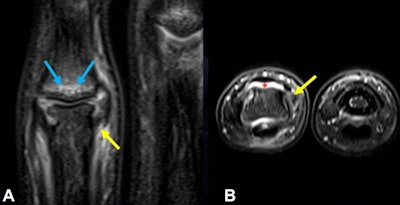

MRI is the best modality for diagnosis and evaluation of soft-tissue trauma in the hand and wrist, particularly in the PIP and MCP joints, and it is useful for evaluating acute and chronic lesions of the stabilizing articular elements (volar plate and collateral ligaments) of the fingers and thumbs, including injuries to the pulley system, they stated.

Dislocations (dorsal, volar, or lateral) are common in ball-handling sports. Dorsal is the most common type, often involving hyperextension with axial loading. Volar plate injuries occur at the distal attachment with/without avulsion fracture of the base of the MCP joint.

Volar (straight volar, lateral volar, or rotatory) may involve force coupled with a volar thrust to the middle phalanx, and fractures/dislocations have a similar mechanism to dorsal dislocation. Volar plate injuries can be isolated or may occur in association with other injuries, such as collateral ligament tears, the researchers explained.

Common injuries to the thumb MCP joint include dorsal dislocations (hyperextension with complete rupture of the volar plate, usually proximally), collateral ligament injuries, and skier's or gamekeeper's thumb (radially directed force on an abducted thumb), they continued.